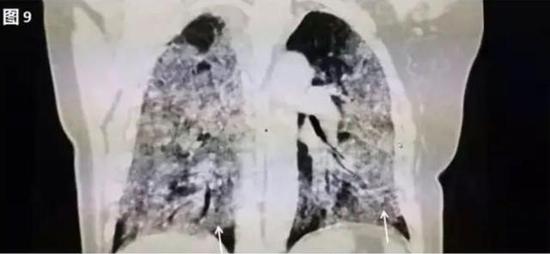

若病毒大量復制,或者患者免疫功能較弱時,會發展為危重癥。此時病毒會攻擊多個肺葉,肺泡損傷彌漫,病變范圍擴大、融合,造成雙肺實變,即從CT上看,患者的肺部呈一大片的白色狀,醫學上稱之為“白肺”。這種情況會嚴重影響肺換氣,患者需要持續吸氧。

▲白肺(圖片來自網絡)

按照國家衛健委發布的新型冠狀病毒肺炎試行第六版診療方案之中的臨床分型,新冠肺炎分為輕型、普通型、重型及危重型。在患者的肺部CT中,輕型者沒有比較明顯的肺炎改變;普通型者以肺部出現局限性斑片狀或很多節段性片狀“病灶”為主(圖②);重型者雙肺可出現較多的白色小斑片“病灶”,部分融合成大片狀“病灶”(圖③);危重型者會有“白肺”表現(圖④)。

▲從上到下依次為普通型、重型及危重型新冠肺炎患者的肺部CT表現(圖片來自網絡)